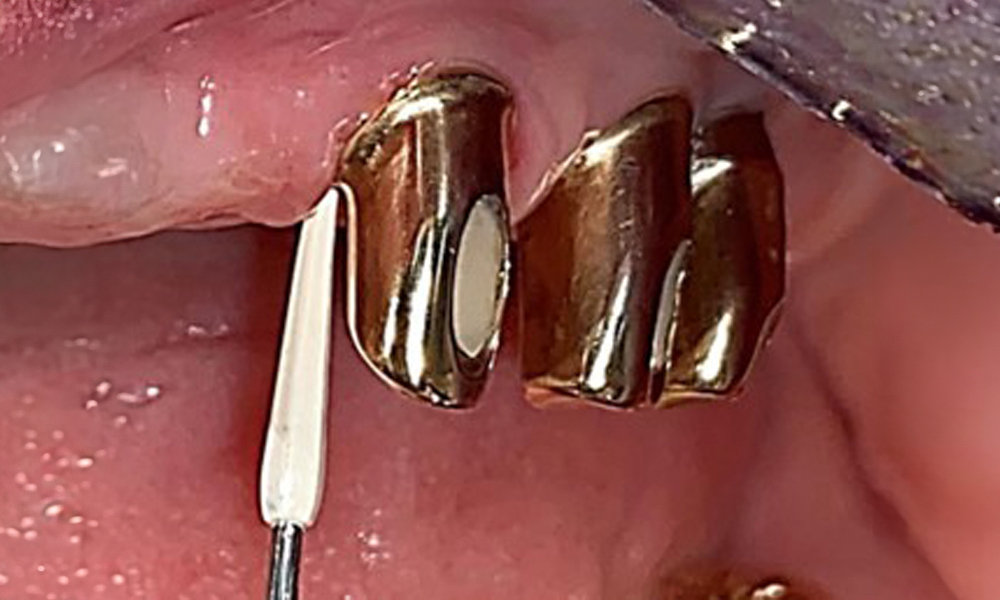

Darstellung einer Peek-Ultraschallspitze (hier Proxeo Ultra, Firma W&H) zur Bearbeitung von Implantatoberflächen bei mineralisierten Belägen (mineralisierte Beläge sind im vorliegenden Fall nicht vorhanden, schematische Darstellung).

Abb. 11: Darstellung einer Peek-Ultraschallspitze (hier Proxeo Ultra, Firma W&H) zur Bearbeitung von Implantatoberflächen bei mineralisierten Belägen (mineralisierte Beläge sind im vorliegenden Fall nicht vorhanden, schematische Darstellung).

Für die Entfernung von Zahnstein und Konkrementen am natürlichen Zahn kann Schall Ultraschall verwendet werden sowie konventionelle Handinstrumente (8). An den Implantaten sind für mineralisierte Beläge Titan- oder Kunststoffküretten (Abb. 10) einzusetzen oder ein Kunststoff- bzw. Peek-Ansatz (Abb. 11) für die Ultraschallbehandlung, um die Implantatoberfläche nicht zu beschädigen.